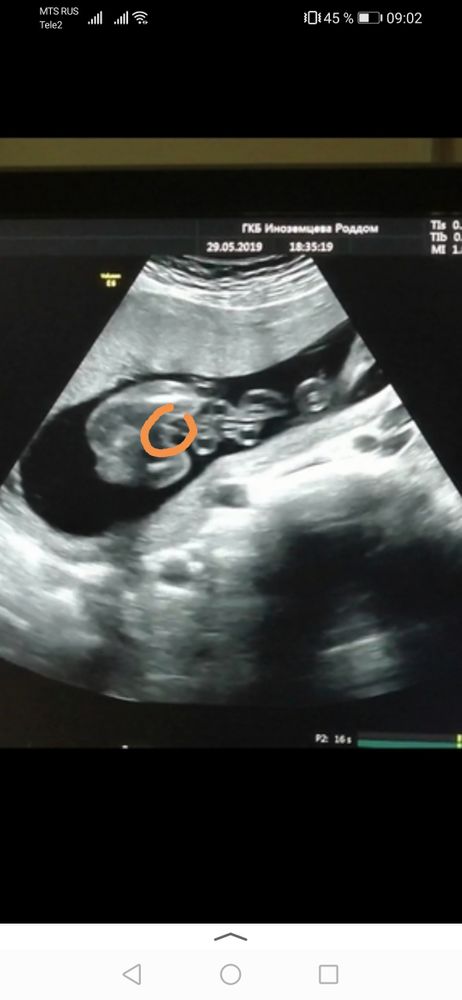

Закрашиваю кружок❤️ Здравствуйте подскажите какой пол у ребёнка? 12 недель